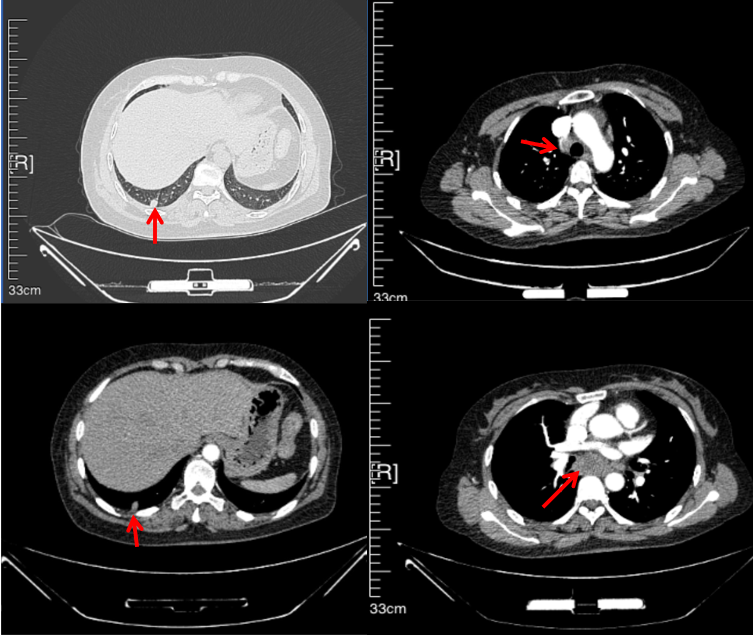

2016年1月复查CT提示支气管截断可见新发小结节,一线治疗采用培美曲塞+DDP方案化疗4周期(培美曲塞3.36,DDP 480mg)。化疗后复查胸部CT:右肺见不规则结节样影,最大层面大小约19mm*8mm,较前比较明显增大,疗效评估PD。2017.3-2017.4予单药多西他赛化疗3周期,疗效评估SD。2018年5月末复查CT提示结节较前增大,评效为PD,2018年6-10月予多西他赛+CBP化疗4周期,疗效评估SD。2022年5月患者出现活动后气短,复查胸部CT示右肺膨胀不良;右侧胸腔积液增多。胸腔积液包埋病理示符合肺腺癌细胞。行NGS基因检测:EML4:exon13-ALK:exon20融合。PD-L1(克隆号22C3)TPS<1%。

临床诊断:右肺上叶恶性肿瘤rT0N0M1a IVA期(第9版分期);恶性胸腔积液。

诊疗经过:2022年5月始口服克唑替尼3个月,出现肝功能异常(DILI 2级伴临床症状),改用恩沙替尼靶向治疗至今,目前评效为维持PR。恩沙替尼应用期间出现轻度肝功能异常(DILI 1级),对症处理后好转。截止目前PFS 33个月。

2018.07

2022.05

2022.08

2023.05

2024.12